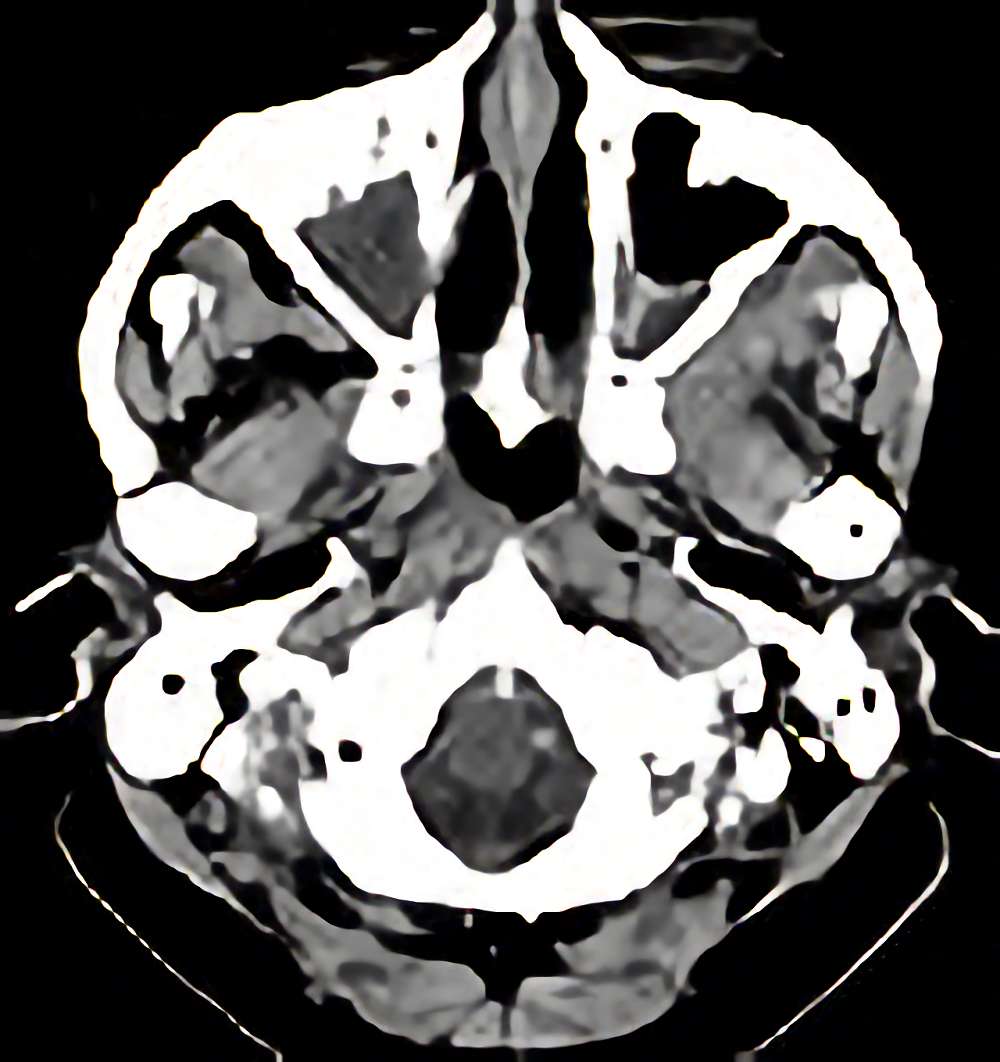

脳腫瘍

断層撮影

手術前1

No.’12_206 手術前1